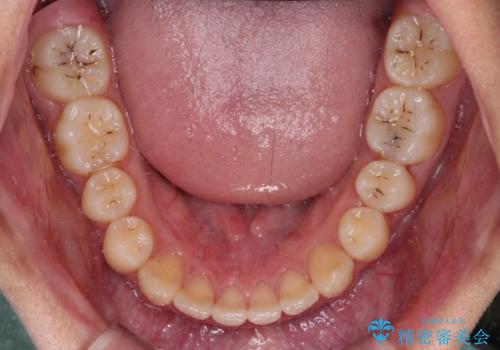

- 前歯のデコボコと隙間を気にして来院された高校生の患者様です。

下顎前歯が上顎前歯を突き上げるような咬み合わせとなっており、その影響で上顎正中に隙間ができている状態でした。

叢生の程度は軽度であり、本人もしっかりと使用する自信があるとのことだったので、インビザラインによる矯正治療を行うこととしました。

突き上げによる隙間を予防する為に、深い咬み合わせを改善するような治療計画としました。咬み合わせを改善させることはできましたが、隙間は後戻りしやすいので、通常の下顎前歯のみではなく、上顎前歯2本もワイヤーで保定を行いました。